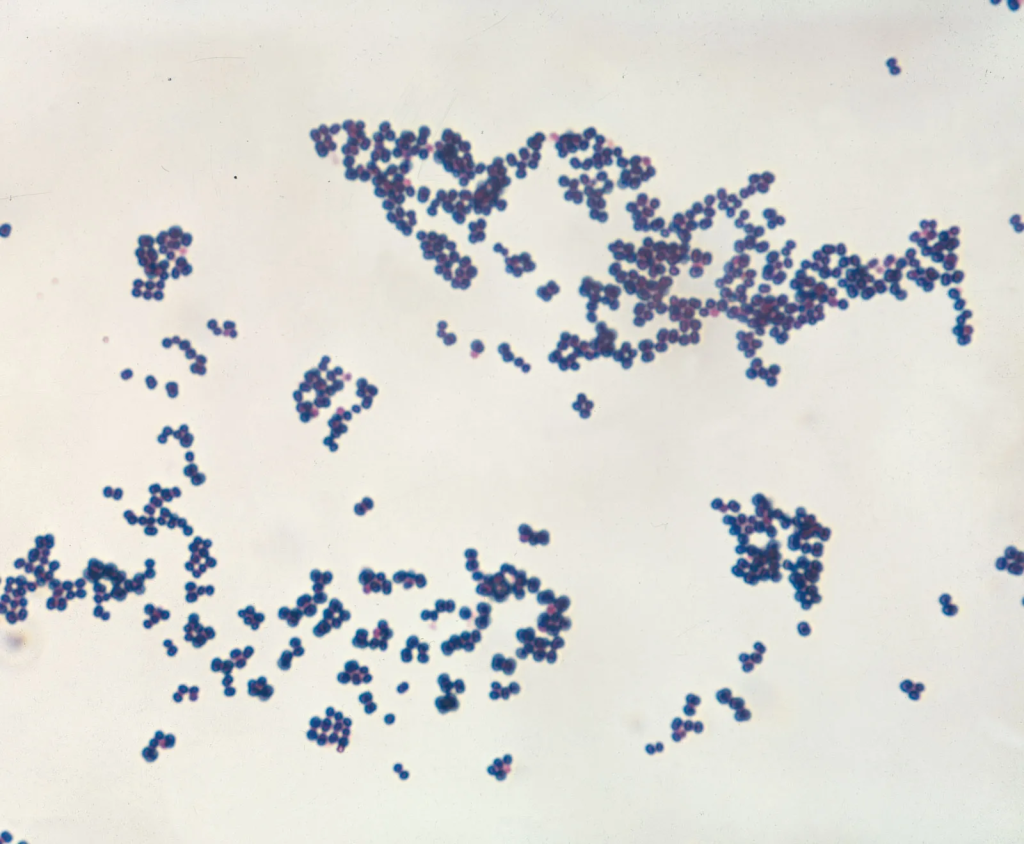

Stafilokoku është një grup bakteresh që jetojnë zakonisht në lëkurë dhe në mukozë te njerëzit. Shumica e tyre nuk shkaktojnë probleme, por disa mund të bëhen patogjenë dhe të shkaktojnë infeksione, veçanërisht nëse lëkura dëmtohet ose sistemi imunitar është i dobësuar. Lloji më i rëndësishëm është stafilokoku i artë, i cili mund të shkaktojë infeksione të lëkurës, infeksione të plagëve, helmime ushqimi dhe në raste më të rënda infeksione në gjak ose në organet e brendshme. Një formë e tij e rezistent ndaj antibiotikëve, e njohur si MRSA, paraqet sfidë të madhe në spitale.

Infeksionet nga stafilokoku përhapen përmes kontaktit të drejtpërdrejtë të lëkurës ose prej sipërfaqeve të kontaminuara. Simptomat variojnë nga skuqje dhe qelb deri te ethe dhe gjendje e rënduar në infeksione sistemike. Diagnoza vendoset përmes kulturës bakteriale dhe antibiogramit, ndërsa trajtimi bazohet në antibiotikë të zgjedhur sipas ndjeshmërisë së bakterit. Parandalimi luan rol kyç dhe përfshin higjienë të rregullt të duarve, trajtimin e plagëve dhe përdorimin e kujdesshëm të antibiotikëve për të shmangur rezistencën.